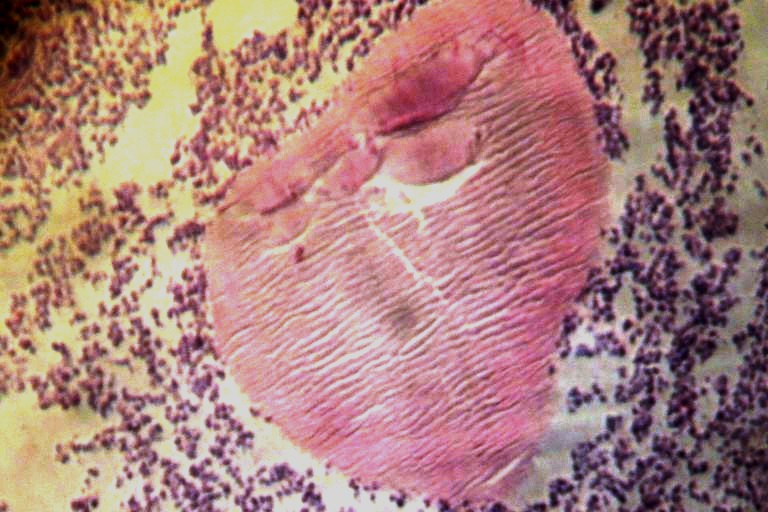

Fig 4: Streptomyces somaliensis actinomycotic granule (center of picture, H and E stain; x 10)